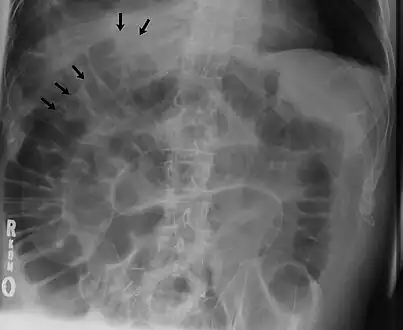

Signs that can be seen on projectional radiography are shown below:

The double wall sign marks the presence of air on both sides of the intestine.[27] However, a false double wall sign can result from two loops of bowel being in contact with one another.[28] The sign is named after Leo George Rigler.[29] It is not the same as Rigler's triad.

a) X-ray of abdomen, showing subdiaphragmatic free air, air outlining the properitoneal fat stripe black arrows b) Cupola sign arrowheads c) Rigler's sign d) chest radiograph showing free air under the diaphragms

Double wall sign. This is a secondary sign of pneumoperitoneum. Patient is supine, and air within the abdomen and lumen of the bowel accentuate both sides of the bowel wall.- Ultrasound finding of pneumoperitoneum known as "peritoneal stripe sign"[32]